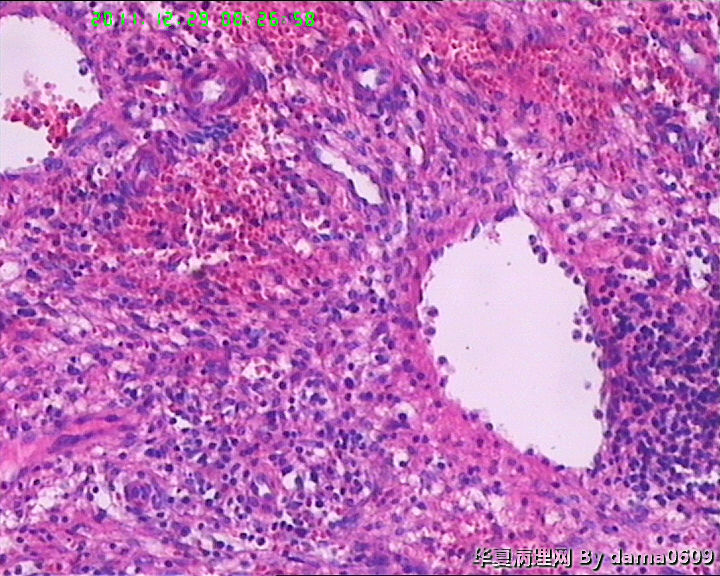

另一为小块囊壁样组织。镜下见卵巢间质内大量淋巴细胞、嗜酸性粒细胞浸润,间质出血。囊壁囊腔一侧见组织细胞、嗜中性粒细胞浸润,小血管增生(图1-9)。局灶见较多的平滑肌组织,内见有异位的子宫内膜组织(图10、11、12)。另于平滑肌组织间见到散在的小腺体(图13~30)。学生不解:1、老年人卵巢内可以出现平滑肌组织,如卵巢门处。此例如此多的平滑肌是正常的吗?   2、平滑肌间的小腺体若是异位的子宫内膜腺体但周围不见内膜间质成分。若非内膜异位腺体,学生又不知如何解释,尤其图19、20、21。请老师们指点迷津。感谢!!

• 感谢老师们一年来的支持,年终岁尾最后一贴,请老师们指教!!图1

图1